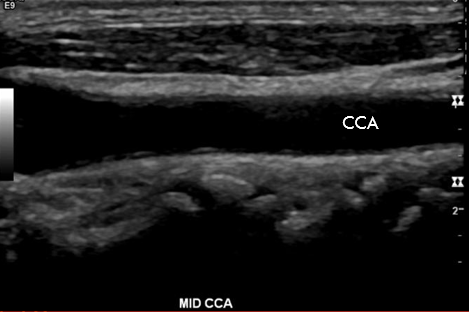

True or False: This image shows a Long CCA sonographic appearance

True